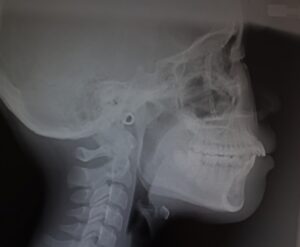

瑞穂市 歯医者 Eライン  吉田歯科院